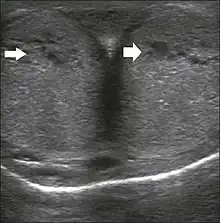

Ultrasonography

Penile ultrasonography with doppler can be used to examine the erect penis. Most cases of ED of organic causes are related to changes in blood flow in the corpora cavernosa, represented by occlusive artery disease (in which less blood is allowed to enter the penis), most often of atherosclerotic origin, or due to failure of the veno-occlusive mechanism (in which too much blood circulates back out of the penis). Before the Doppler sonogram, the penis should be examined in B mode, in order to identify possible tumors, fibrotic plaques, calcifications, or hematomas, and to evaluate the appearance of the cavernous arteries, which can be tortuous or atheromatous.[45]

Erection can be induced by injecting 10–20 μg of prostaglandin E1, with evaluations of the arterial flow every five minutes for 25–30 min (see image). The use of prostaglandin E1 is contraindicated in patients with predisposition to priapism (e.g., those with sickle cell anemia), anatomical deformity of the penis, or penile implants. Phentolamine (2 mg) is often added. Visual and tactile stimulation produces better results. Some authors recommend the use of sildenafil by mouth to replace the injectable drugs in cases of contraindications, although the efficacy of such medication is controversial.[45]

Before the injection of the chosen drug, the flow pattern is monophasic, with low systolic velocities and an absence of diastolic flow. After injection, systolic and diastolic peak velocities should increase, decreasing progressively with vein occlusion and becoming negative when the penis becomes rigid (see image below). The reference values vary across studies, ranging from > 25 cm/s to > 35 cm/s. Values above 35 cm/s indicate the absence of arterial disease, values below 25 cm/s indicate arterial insufficiency, and values of 25–35 cm/s are indeterminate because they are less specific (see image below). The data obtained should be correlated with the degree of erection observed. If the peak systolic velocities are normal, the final diastolic velocities should be evaluated, those above 5 cm/s being associated with venogenic ED.[45]